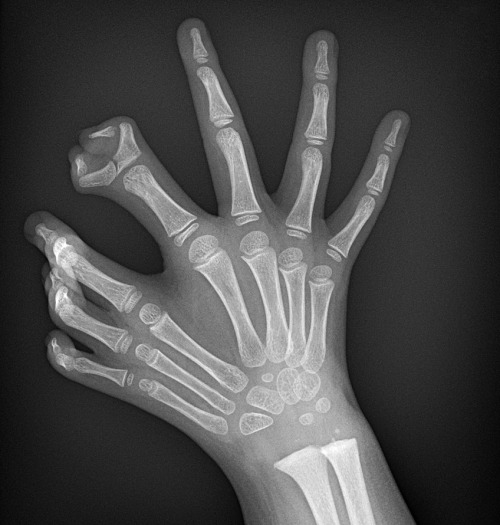

The above is a polydactyl claw x-ray. This congenital anomaly causes people to be born with more than the usual number of fingers/toes.